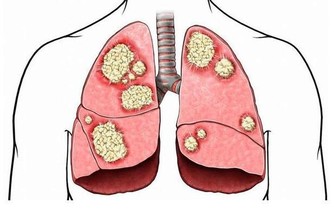

睡錯方向可能帶來的健康問題

如果長期選擇不適合自己的睡姿,可能會影響身體健康,例如:

- 消化不良與胃食道逆流:右側睡可能會加重胃酸逆流的症狀。

- 心血管壓力:仰睡可能讓心臟負擔增加,影響血液循環。

- 脊椎與關節疼痛:錯誤的睡姿會造成頸椎、腰椎與肩膀疼痛,影響長期健康。

- 呼吸問題:仰睡與趴睡可能影響氣道暢通度,導致打鼾或呼吸不順。